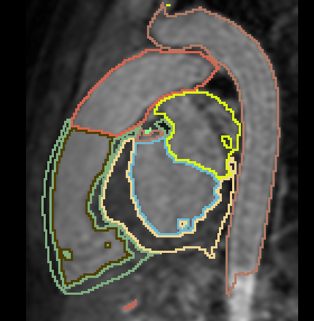

Interactive Deep Learning for Congenital Heart Disease Segmentation

- Aim: segment all cardiac chambers and great vessels from cardiac MRI, for children with congenital heart disease.

- 20 training cases + large anatomical variability - remains a challenge for automatic segmentation.

- Approach: Integrate some interaction from the user, e.g. scribbles or landmarks.

- Already have framework for interactive segmentation. Currently testing using scribbles for aorta segmentation.